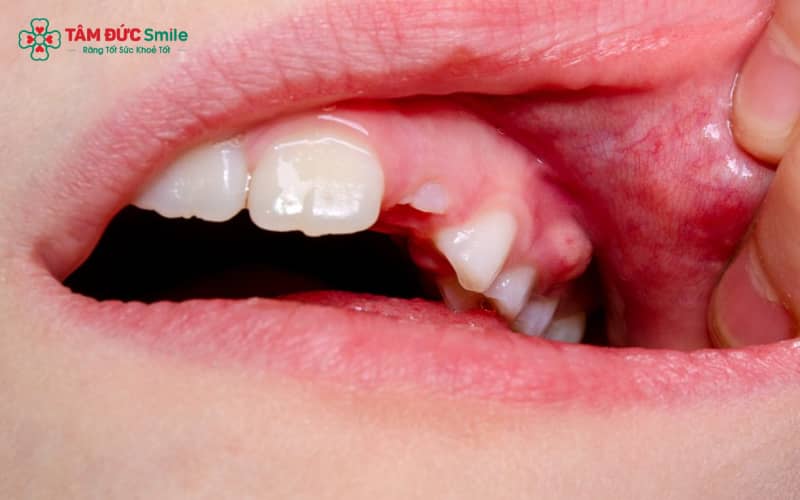

2.5. Ảnh hưởng từ răng khôn mọc lệch

Răng khôn mọc lệch, mọc ngầm thường gây chèn ép mô nướu, làm thức ăn dễ mắc kẹt và vi khuẩn phát triển. Hệ quả là sưng lợi, đau nhức vùng chân răng, thậm chí lan sang các răng kế cận.